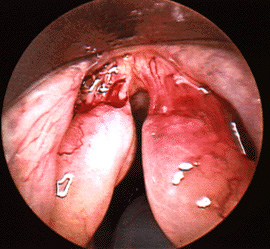

Close up of a large right vocal cyst

This image shows a close up view of a larger cyst in a different individual. This photograph was taken at the time of surgery for removal of the cyst. Notice that the left vocal fold is slightly thickened immediately opposite the cyst. This thickening has developed in response to the cyst, and should resolve spontaneously after removal of the cyst.‌